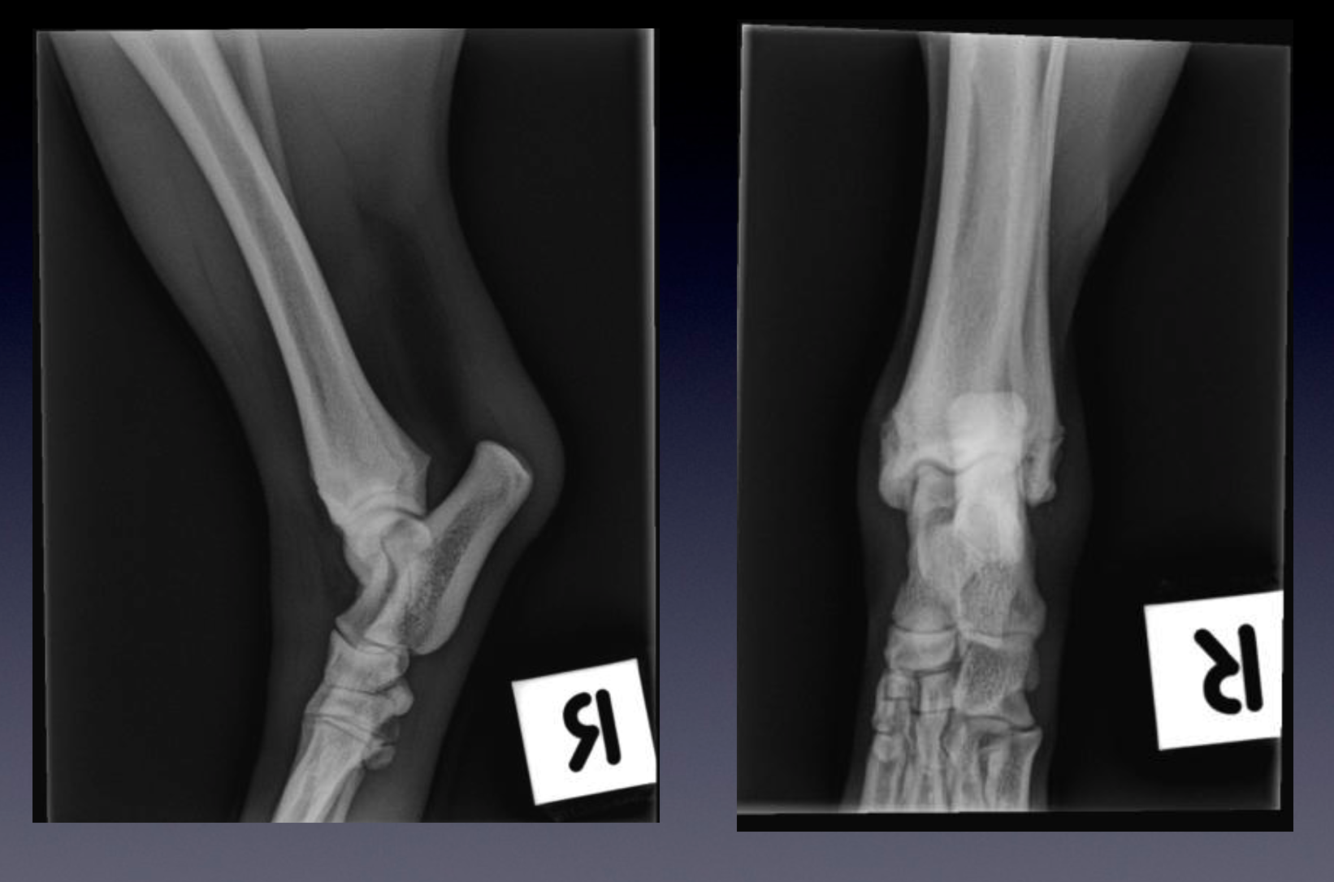

Patient number 240208 - Normal Canine tarsus

Mediolateral and dorsoplantar projections are provided.

Note the physes (‘growth plates’) of the tibia and fibula. They are almost closed.

The physis of the tuber calcanei is already completely closed.

Note that despite the complex anatomy of the tarsus, the borders of each joint space and each bone

are smooth.

Can you name all boney structures on the images?

Note the close interdigitation of the trochlear ridges of the talus, with the distal aspect of the tibia.